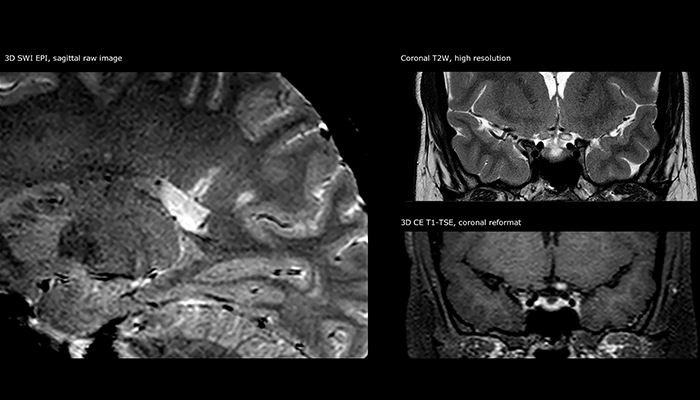

When multiple sclerosis (MS) is suspected, clinicians need a diagnosis early on, so treatment can begin as soon as possible. “A challenge for imaging is that MS lesions in the brain and spine may be very small,” says Dr. Savatovsky. “We need precise imaging to tell exactly where the lesion is, so we need high quality, very high resolution images, preferably in 3D[1]. We need to know if a high T2 signal intensity is suggestive of MS or just aspecific. And we want to visualize active lesions very well.”

“Ingenia 3.0T provides us very good image quality with high SNR, even if we push the resolution. For example, in FLAIR images we may have an isotropic resolution of 0.9 mm. Ingenia allows us to use 3D T1 TSE with BrainView, which has a better sensitivity than 2D spin echo imaging[2] and 3D gradient echo imaging. Ingenia also provides highly reproducible exams, which is important in MS imaging so that follow-up exams at different time points are done the same way.”

For MS imaging in the brain, Dr. Savatovsky uses 3D FLAIR as the basic sequence to visualize the lesions and assess the situation and lesion load. “We count the lesions in each location to determine if the criteria of the disease are fulfilled. We use a T2-weighted sequence because our neurologists are used to it. We compare the lesion load on FLAIR with a 3D T1 post-contrast sequence to help us determine whether lesions are old or new. We typically administer the contrast before the patient enters the machine because it shortens the examination time and allows to visualize active lesions that tend to be more visible after several minutes. When a differential diagnosis is difficult, we add sequences such as susceptibility imaging, because some focal MS lesions have a small vein in the center[3].”